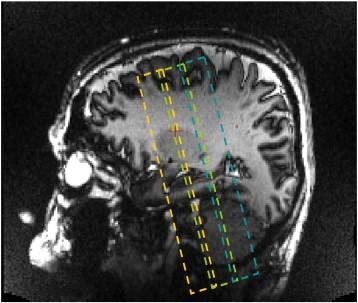

In Alzheimer's disease (AD), the hippocampus is an early site of tau pathology and neurodegeneration. Histological studies have shown that lesions are not uniformly distributed within the hippocampus. Moreover, alterations of different hippocampal layers may reflect distinct pathological processes. 7 T MRI dramatically improves the visualization of hippocampal subregions and layers. In this study, we aimed to assess whether 7 T MRI can detect volumetric changes in hippocampal layers in vivo in patients with AD. We studied four AD patients and seven control subjects. MR images were acquired using a whole-body 7 T scanner with an eight channel transmit-receive coil. Hippocampal subregions were manually segmented from coronal T2*-weighted gradient echo images with 0.3 × 0.3 × 1.2 mm3 resolution using a protocol that distinguishes between layers richer or poorer in neuronal bodies. Five subregions were segmented in the region of the hippocampal body: alveus, strata radiatum, lacunosum and moleculare (SRLM) of the cornu Ammonis (CA), hilum, stratum pyramidale of CA and stratum pyramidale of the subiculum. We found strong bilateral reductions in the SRLM of the cornu Ammonis and in the stratum pyramidale of the subiculum (p < 0.05), with average cross-sectional area reductions ranging from -29% to -49%. These results show that it is possible to detect volume loss in distinct hippocampal layers using segmentation of 7 T MRI. 7 T MRI-based segmentation is a promising tool for AD research.

在阿尔茨海默病(AD)中,海马体是 tau 病理学和神经退行性变的早期部位。组织学研究表明,病变在海马体内不是均匀分布的。此外,不同海马层的改变可能反映了不同的病理过程。7T MRI 极大地提高了海马亚区和层的可视化程度。在这项研究中,我们旨在评估 7T MRI 是否可以在 AD 患者体内活体检测海马层的体积变化。我们研究了 4 名 AD 患者和 7 名对照受试者。使用全身 7T 扫描仪和 8 通道发射接收线圈采集 MR 图像。使用区分神经元体丰富或贫乏的层的协议,从冠状 T2*-加权梯度回波图像手动分割海马亚区,分辨率为 0.3×0.3×1.2mm3。在海马体区域中分割了五个亚区:齿状回的内分子层、放射层、腔隙层和分子层(SRLM)、门区、CA 的锥体层和 subiculum 的锥体层。我们发现 SRLM 的双侧明显减少,以及 subiculum 的 CA 的锥体层(p<0.05),平均横截面积减少范围从-29%到-49%。这些结果表明,使用 7T MRI 的分割可以检测到不同海马层的体积损失。基于 7T MRI 的分割是 AD 研究的有前途的工具。